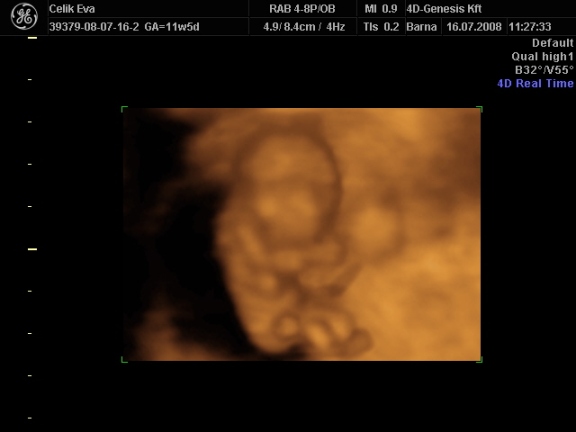

3d-s babafotók:

Kép